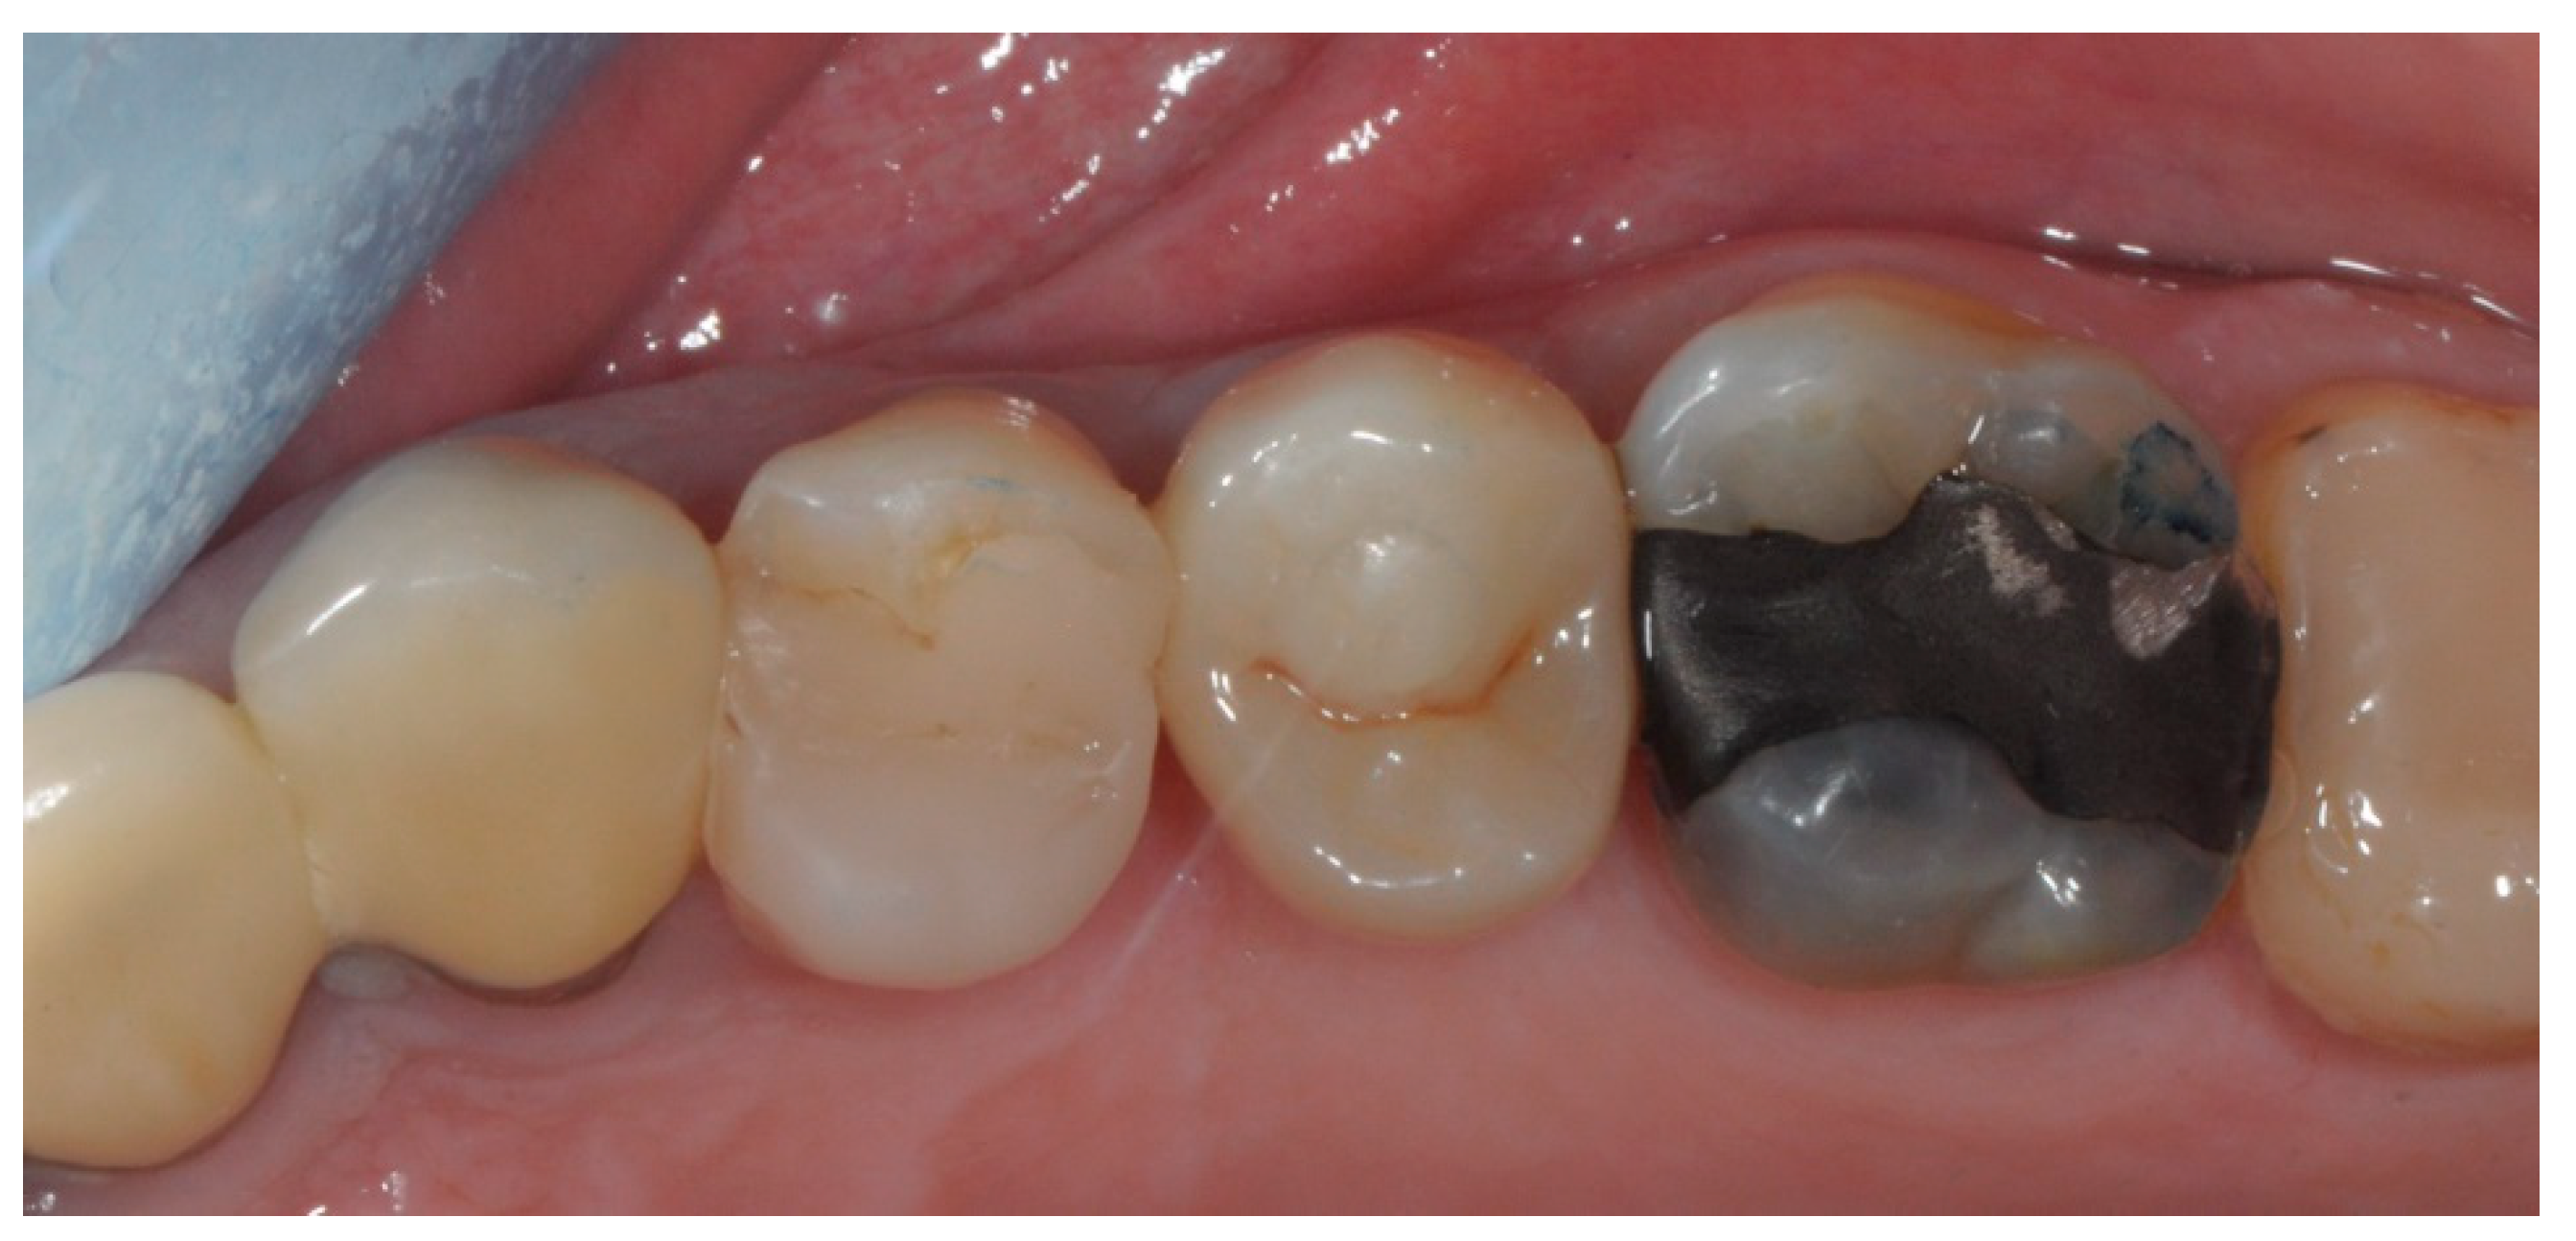

2.3. Prosthetic Protocol